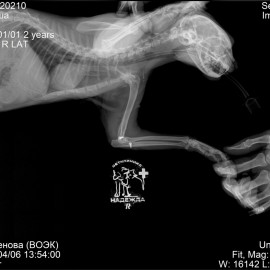

Кот Тимоша. Жалобы на хромоту на правую переднюю лапу в течение нескольких дней. После осмотра и рентгенографии был поставлен диагноз: вывих правого локтевого сустава. Была проведена операция: остеосинтез правого локтевого сустава.

Снимок 1 до операции